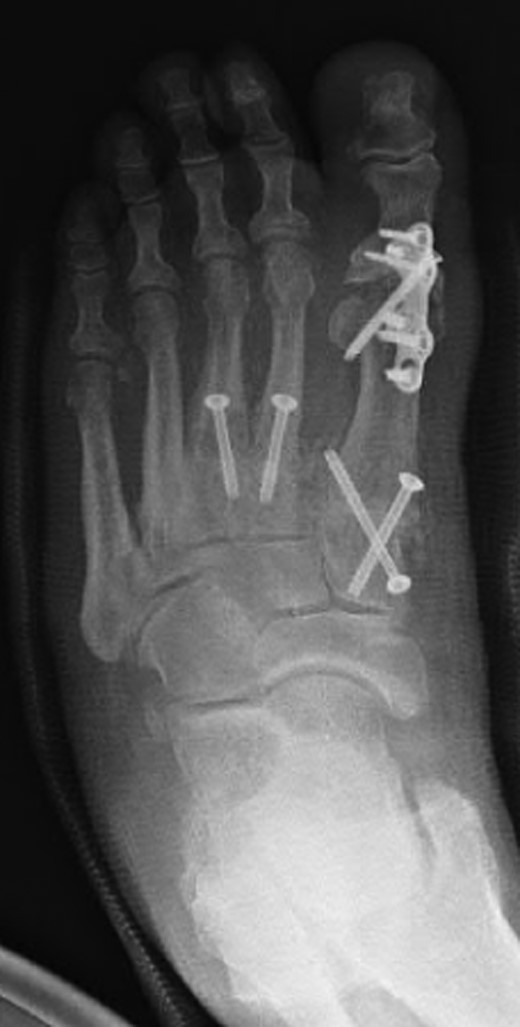

Oblique radiograph of the left foot following first MTPJ and first, second and third TMTJ fusions.

Dorsoplanter radiograph of the left foot following first MTPJ and first, second and third TMTJ fusions.

The patient had undergone previous diagnostic and therapeutic corticosteroid injections into his first, second and third TMTJs, temporarily improving the mid-foot pain. The patient wanted complete pain resolution and so underwent arthrodesis of these joints and the first MTPJ (Figs 6 and 7). Operative findings confirmed radiographic findings with the presence of an additional middle cuneiform covered with degenerate cartilage proximally and distally.

Another clinical significance could arise in the case of a second TMTJ arthrodesis. The dilemma is presented as to whether or not fusion be performed between the second metatarsal base and the additional ossicle (Figs 6 and 7), or to span the additional ossicle fusing the second metatarsal to the middle cuneiform. Either way, careful assessment of the anatomy must be performed preoperatively to ensure that all joint surfaces are prepared and arthrodesed appropriately.